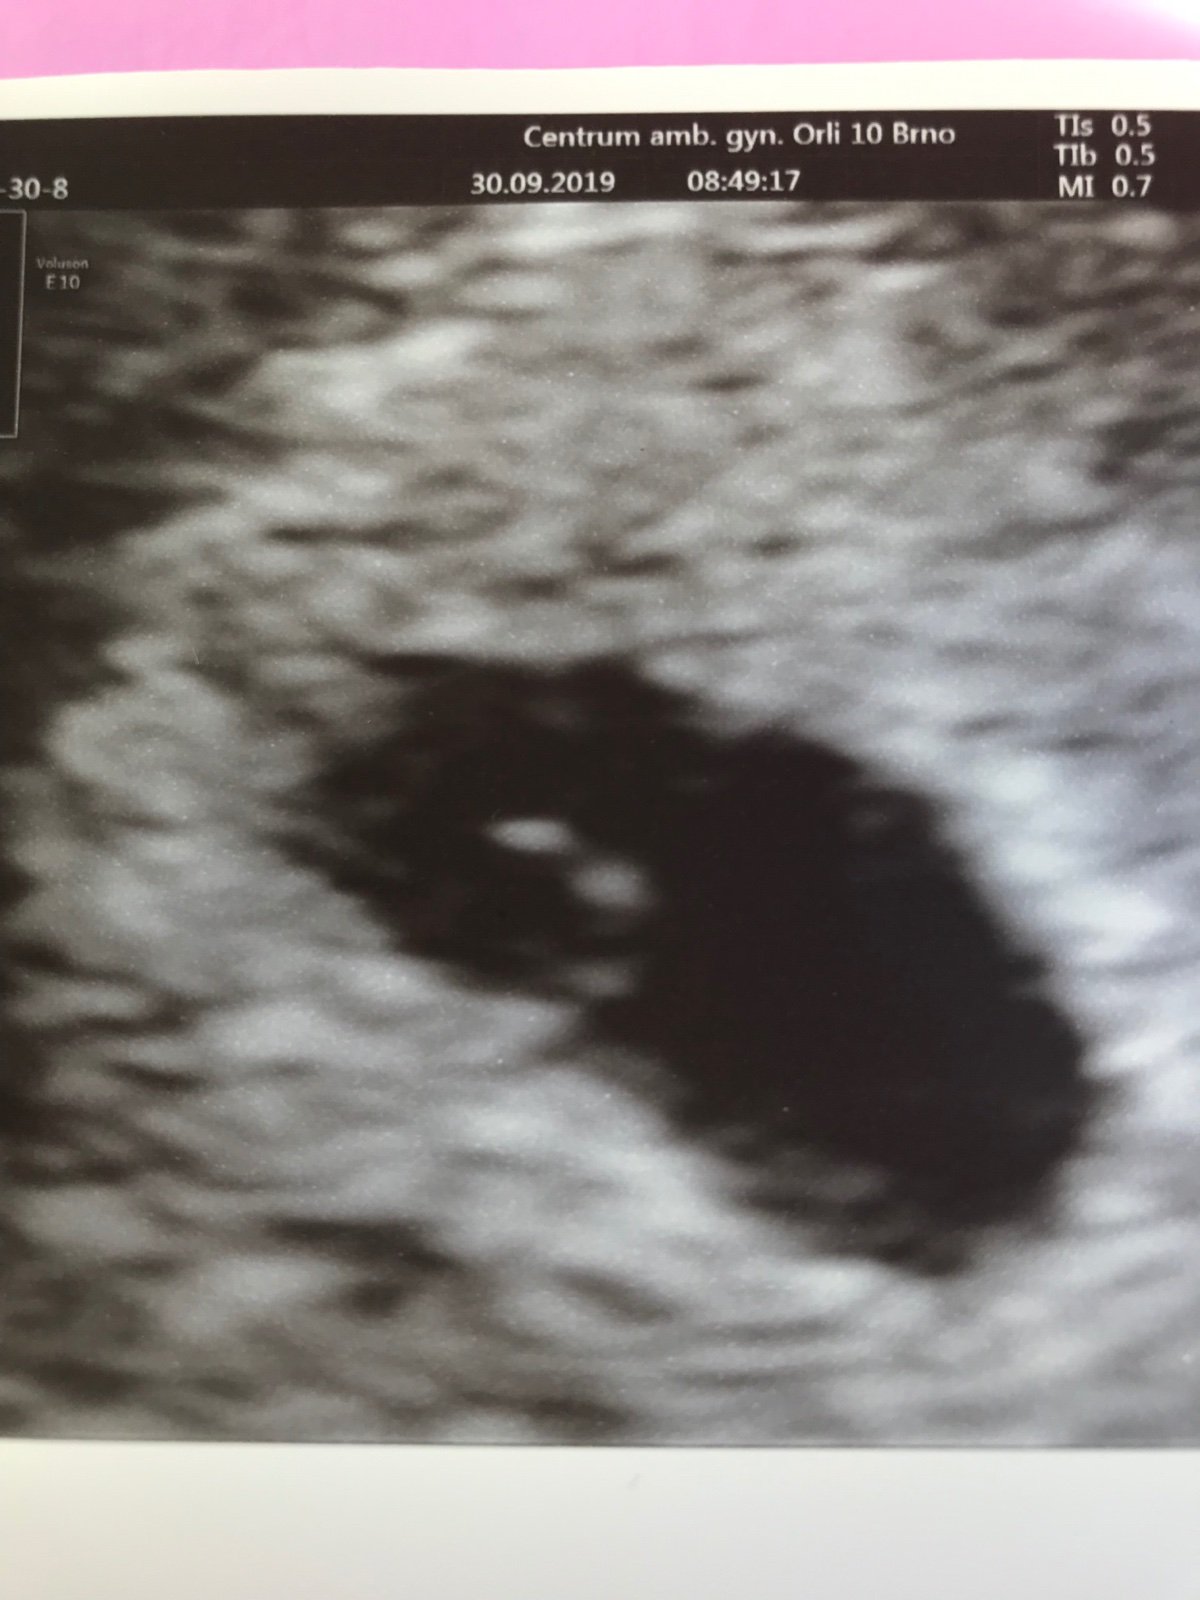

Ahoj holky 🙂 dnes jsem byla u gynekologa,ze je konec mesice s neschopenkou...tak zrovna i mu rict jak teda to dopadlo...

Tak se ani neptal jestli chci do prace a nechal ji dal.Pry tak na to i kouknem...

Odpovida 5tt

Jdu tam 21.10.